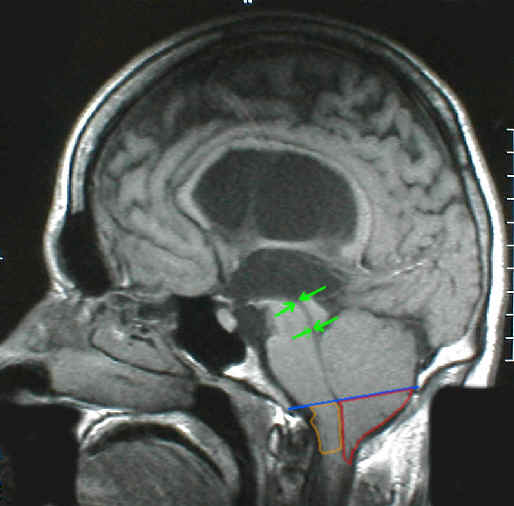

Eine Veränderung die isoliert oder in Kombination mit anderen Mißbildungen vorkommen kann. Insbesondere sehr häufig bei offenem Rückenmark (Spina bifida / Meningomyelocele). Das charakteristische daran ist, dass die hintere Schädelgrube, in der normalerweise das Kleinhirn und das Stammhirn liegen quasi zu klein ist für diese Hirnanteile. Aus diesem Grund verlagern sich diese Hirnanteile nach unten in den oberen Rückenmarkskanal. Das Bild oben zeigt mit der blauen Linie das Niveau an auf dem die hintere Schädelgrube nach unten hin endet. Unschwer ist zu erkennen, dass Anteile des Kleinhirns (rot umrandet) und Anteile des Stammhirns (gelb umrandet) dieses Niveau deutlich unterschreiten. Zusätzlich besteht eine Aquäduktstenose (grüne Pfeile). Die Kombination von Chiari-Mißbildung und Aquäduktstenose ist gar nicht selten anzutreffen, denn durch die Enge in der hinteren Schädelgrube wird der obere Kleinhirnanteil auch häufig nach oben in Richtung des Großhirns verschoben. Da die anatomische Begrenzung der hinteren Schädelgrube zum Großhirn hin (das Tentorium) typischerweise auch häufig sehr schwach ausgebildet ist, wird diese Verlagerung des Kleinhirnes auch noch gefördert. Durch die Verlagerung von Kleinhirnanteilen nach oben wird das Mittelhirn gequetscht und in ihm liegt der Aquädukt, der dabei ebenfalls gequetscht wird.

Das Bild zeigt einen Okklusionshydrocephalus: eine gutartige Geschwulst (Kolloidzyste) behindert den Liquorabfluß aus den Seitenventrikeln in den III.Ventrikel. Die roten Pfeile zeigen den Tumor, die gelben Pfeile deuten an, wo der Liquor eigentlich durchfließen sollte, nämlich durch die For. Monroi, die aber durch den Tumor verlegt sind.